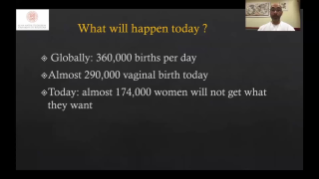

Kad?n sa?l??? tarama ziyaretlerinde yĂŒksek dĂŒzeyde hasta hacimlerini desteklemek i?in, optimize edilmi? OBG i? ak??lar? gerekir. ?rne?in, merkezi sinir sistemi (CNS) malformasyonlar?, en yayg?n g?rĂŒlen konjenital anormalliklerden biridir. K?tĂŒ fetĂŒs pozisyonu gibi, ?e?itli g?rĂŒntĂŒleme durumlar? nedeniyle, 2 boyutlu ultrasonda MSPâyi elde etmek ?zellikle zordur. Bu nedenle, otomatik alg?lama ve ?l?ĂŒmler, tarama verimlili?ini bĂŒyĂŒk ?l?ĂŒde art?rabilir.